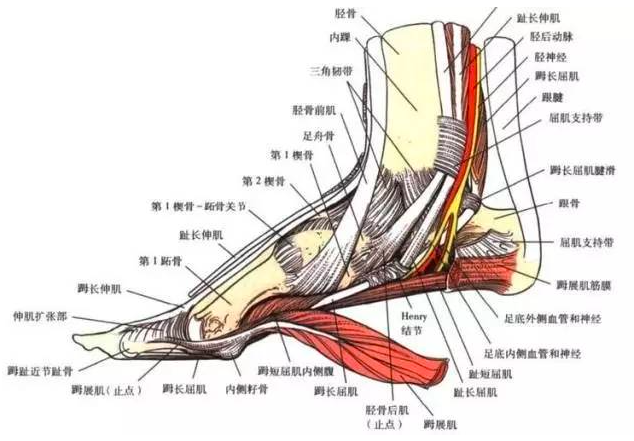

踝关节解剖分析

图片尺寸737x837

值得收藏踝关节解剖分析高清图文详解

图片尺寸660x401